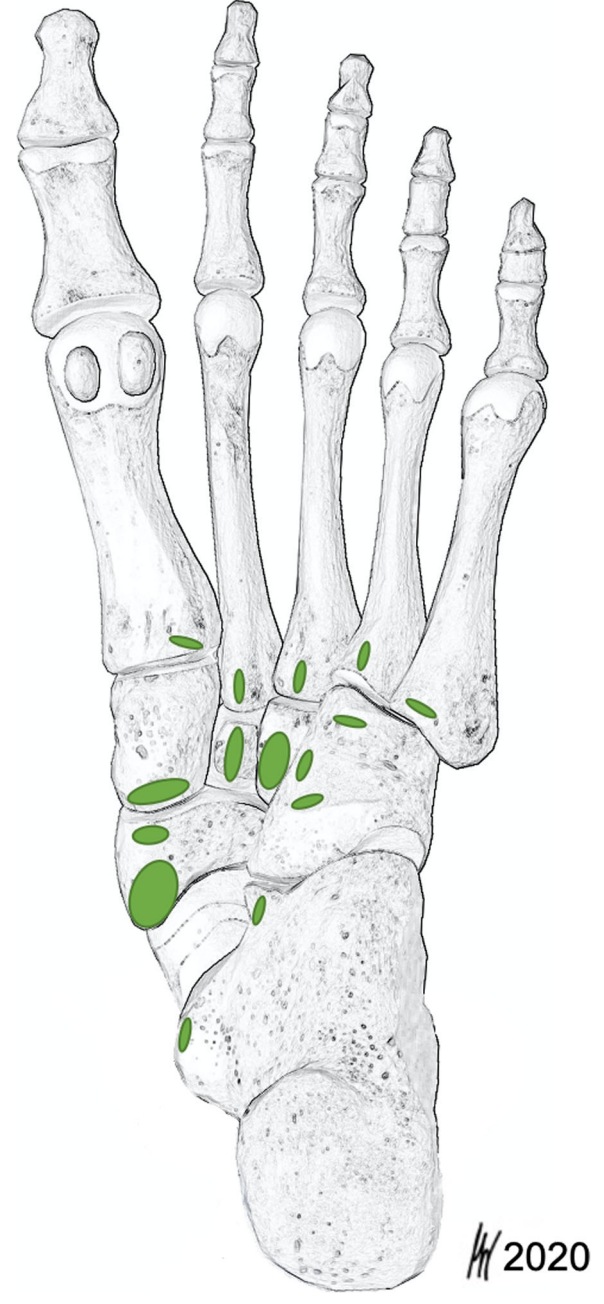

https://doi.org/10.1186/s40634-019-0171-y

https://doi.org/10.1186/s13047-020-00392-1

최신 해부학 연구 논문을 보면

후경골근건은 주상골 하나에만 붙는 게 아니라,

마치 나무뿌리처럼 여러 갈래로 뻗어나가

발바닥 깊숙한 곳의 여러뼈에 붙어있었습니다.

한 연구에서는 무려 8개의 다른 뼈에까지

뻗어나가는 모습이 확인되기도 했죠.

또한, 가장 중요한 부착 지점인 주상골에도

단순히 옆에 붙는 게 아니라

발바닥 쪽 아래에서 받쳐주는 형태로붙어있는 경우가 63%나 됐습니다.

후경골근건은 하나의 기둥이 아닌,

*발바닥 전체를 움켜쥐는

**'뿌리'의 역할을 하는 것이죠.*이게 왜 중요할까요?

사람마다 힘줄이 붙는 모양과 개수가

천차만별이라는 뜻입니다.

누구는 2갈래, 누구는 4갈래,

또 누구는 8갈래로 붙어있을 수 있는 거죠.